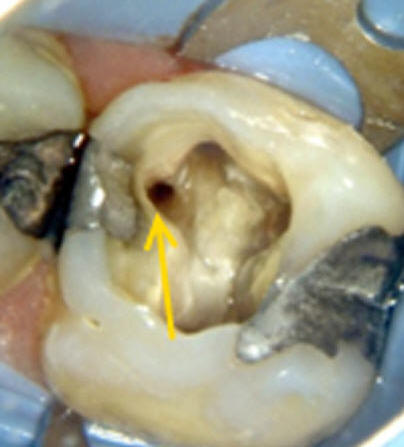

Cuarto conducto en molares superiores (Color amarillo conducto mesio-palatino)

Primer molar superior

Presenta tres raíces, las cuales se distribuyen dos vestibulares y una palatina.

La raíz mesiovestibular es achatada en sentido mesiodistal y amplia en sentido vestibulopalatino.El conducto mesiovestibular con frecuencia es curvo y de sección en forma de hendidura. La existencia de dos conductos en esta raíz, puede presentar la siguiente configuración:

• uno vestibular (Color azul)

• y el otro palatino (Color amarillo)

Estos conductos pueden unirse a distintos niveles, terminando en un foramen único o ser de trayectoria independiente hasta el ápice y terminar en forámenes separados. Son atrésicos y de difícil tratamiento en especial el palatino.